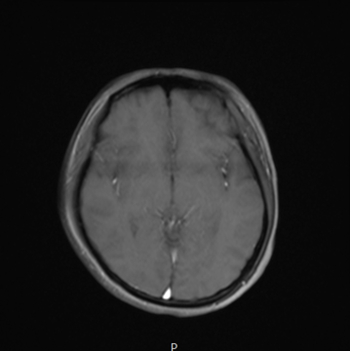

진통제를 달고 살았지만 전혀 나아지지 않는 두통 때문에

대학병원까지 가서 MRI를 찍었지만

결과는 '정상'

<Fig 1. 이상 소견 없는 뇌 MRI>

그리고 또 다른 특징이 있었어요.